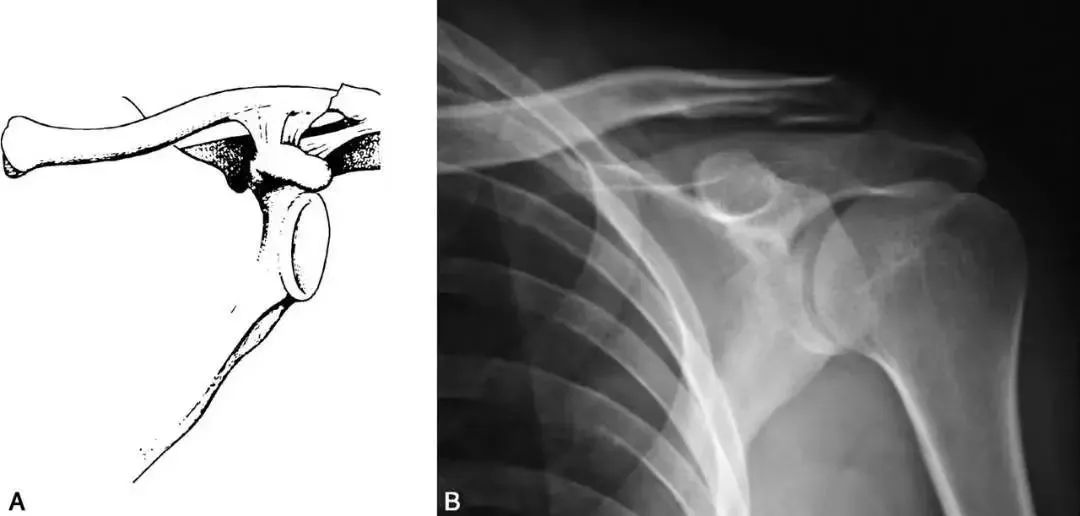

Ⅰ型為中1/3骨折。

Ⅱ型為外1/3骨折,其中Ⅱ型又分成5種類型:

01.韌帶間骨折,通常無(wú)明顯移位或僅輕度移位

02. 喙鎖韌帶內(nèi)側(cè)骨折,其中又根據(jù)韌帶的完整性分為A亞型(錐狀韌帶和斜方韌帶完整,附著于遠(yuǎn)骨折端)和B型(錐狀韌帶斷裂而斜方韌帶完整)

A亞型

B亞型